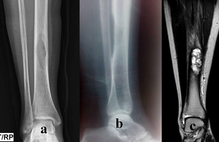

Superficial incisions were made to dissect the skin and deep fascia off completely. The superior and inferior extensor retinacula were cut to expose the tendons. The tendons of the extensor digitorum longus, tibialis anterior, extensor hallucis longus, fibularis longus, and fibularis brevis were cut at their insertions. The muscle belly of the extensor digitorum brevis and its tendons were cut to expose the underlying bones and ligaments. The length of the foot was measured using a ruler from the most posterior end of the calcaneus to the most anterior end of the second distal phalanx. Its width was measured with a ruler at the level of the metatarsal heads. The subtalar joint was cleaned with a probe to expose the CL clearly. The width and height of the cervical ligament (Figure 1-2) were measured. Its thickness was measured at the superior anterior, superior posterior, inferior anterior, inferior posterior and center points with a digital caliper (Hawk Inc., Cleveland, Ohio). The width and height of the talar neck were measured using a digital caliper (Hawk Inc., Cleveland, Ohio). The body of the talus was cut in the frontal plane and its proximal portion was removed to expose the ITCL (Figure 3). Descriptions of the ITCL were recorded for each cadaver.

The ITCL (Figure 3) was observed as a bundle of fibers that spanned across the entire width of the sinus tarsi. Its striated bundle of fibers was oriented in a superomedial to inferolateral fashion. The angles of the ITCL were greater in some cases than others. The ITCL overlaps with the CL in the sinus tarsi, but the distinction between the two ligaments is apparent from the orientations of their fibers. The CL was also situated anteriorly with respect to the ITCL in all of the cadavers studied.